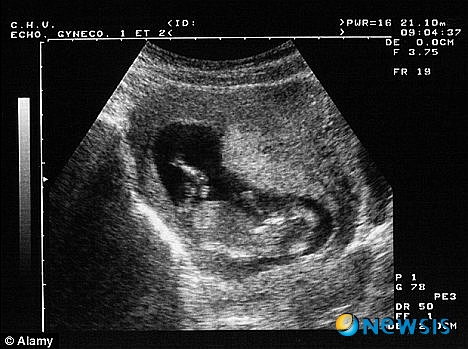

【서울=뉴시스】미 민주당의 린 바흐만 의원이 낙태 반대 법안을 제출하면서 임신 9주 된 태아의 심장 박동 소리를 증거 자료로 제출했다. 사진은 임신한 태아의 초음파 사진 촬영 모습. <사진 출처 : 英 데일리 메일 웹사이트>

【서울=뉴시스】유세진 기자 = 오하이오 주정부 민주당 의원 린 바흐만이 낙태 반대를 주제로 한 법정 심리에서 태아의 심장 소리가 들릴 때에는 낙태를 금지하도록 하는 법안을 상정했다고 영국 데일리메일이 2일 보도했다.

법정에서는 기독교 지지단체가 초음파로 9주와 15주 된 태아를 찍어 오하이오 법정에 반낙태 법안을 지지하기 위한 증거로 쓰여졌다. 태아의 심장 박동은 흑백이 아닌 색으로 표현됐다.

15주 된 태아의 심장 박동은 비교적 찾기 쉬웠으나 9주 된 태아의 경우는 심장 박동을 감지하기가 상대적으로 어려웠다.